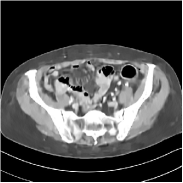

Fig. 2 shows a test example reconstructed using various methods.

Refer to caption

Figure 2: Reconstructions of slice 100 from patient L192 using various methods. The display window is [800 1200] HU.

We observe that PWLS-EP reduces the severe noise and streak artifacts observed in the low-dose FBP images, and the transform learning-based method PWLS-ULTRA further suppresses noise and reconstructs more details of the image such as the zoom-in areas. However, both methods have some blurry artifacts. The standalone FBPConvNet method heavily removes noise and streak artifacts, while introducing several artificial features (e.g., feature indicated by the arrow in the top-right box in Fig. 2). WavResNet denoises the image without introducing artifical features, but still retains some streaks around image boundaries and blurs some details (e.g., feature indicated by the arrow in the bottom-left box in Fig. 2). The state-of-the-art MAP-NN method performs slightly better than WavResNet in terms of suppressing streak artifacts, while it still loses some details as indicated in the zoomed regions. The competing plug-and-play unrolled method—ADMM-Net with WavResNet denoiser—outperforms the standalone WavResNet method, but still has some streak artifacts and blurred details. Compared to these methods, the proposed SUPER methods (SUPER-WRN-EP, SUPER-WRN-ULTRA, SUPER-FCN-EP, and SUPER-FCN-ULTRA) improve the reconstruction quality in terms of removing noise and artifacts, and recovering details more precisely. Two other example comparisons are included in the supplement (Fig. 10 and Fig. 11).